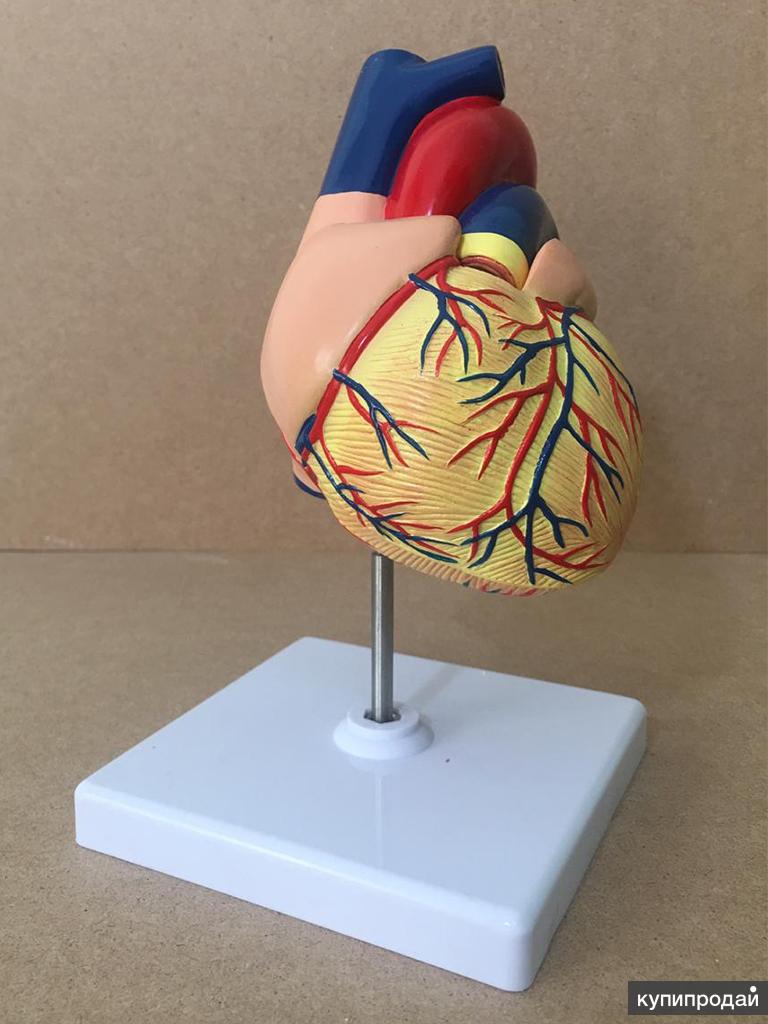

Фотографии и 3D-модели анатомии сердца человека